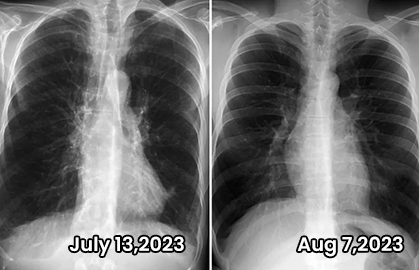

90% of COPD patients reported their lung function returned to normal and their breathing became smoother after treatment.